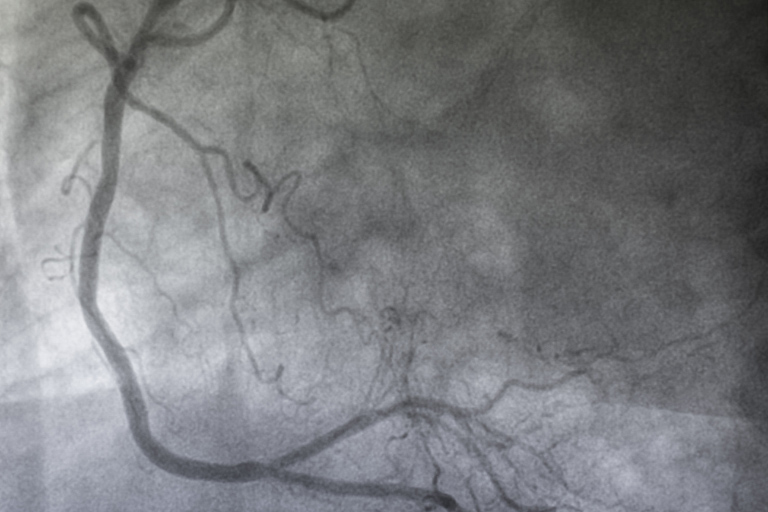

Ob Schaufensterkrankheit oder Krampfadern, Vorsorgeuntersuchung oder Kontrolle nach Gefäßoperationen – der Ultraschall ist das Mittel der Wahl für strahlenfreie Untersuchungen der Gefäße. Sowohl in angiologischen und phlebologischen Praxen als auch in großen Kliniken mit Gefäßchirurgien spielt Ultraschall eine wesentliche Rolle im Untersuchungsalltag. Für ergonomische Handhabung und kristallklare Diagnostik sorgen Ultraschallgeräte von Fischer med. Technik – entdecken Sie jetzt unser Angebot.

In der Angiologie steht bei Untersuchungen eine Ultraschallfunktion klar an der Spitze: Die Duplexsonographie kombiniert das Beste aus Dopplersonographie und regulären Ultraschalluntersuchungen und liefert klare Bilder von Gefäßstruktur und Blutfluss in Echtzeit. Das unsere Ultraschallgeräte für Gefäßkliniken mit funktionellen und hochwertigen Duplex-Programmen ausgestattet sind, ist für uns also eine Selbstverständlichkeit. Sinnvolle Extra-Funktionen und Speichermöglichkeiten für regelmäßige Arbeitsabläufe machen die Ultraschall-Diagnostik von Venen und Arterien zu einer Bereicherung für Ihre Klinik.